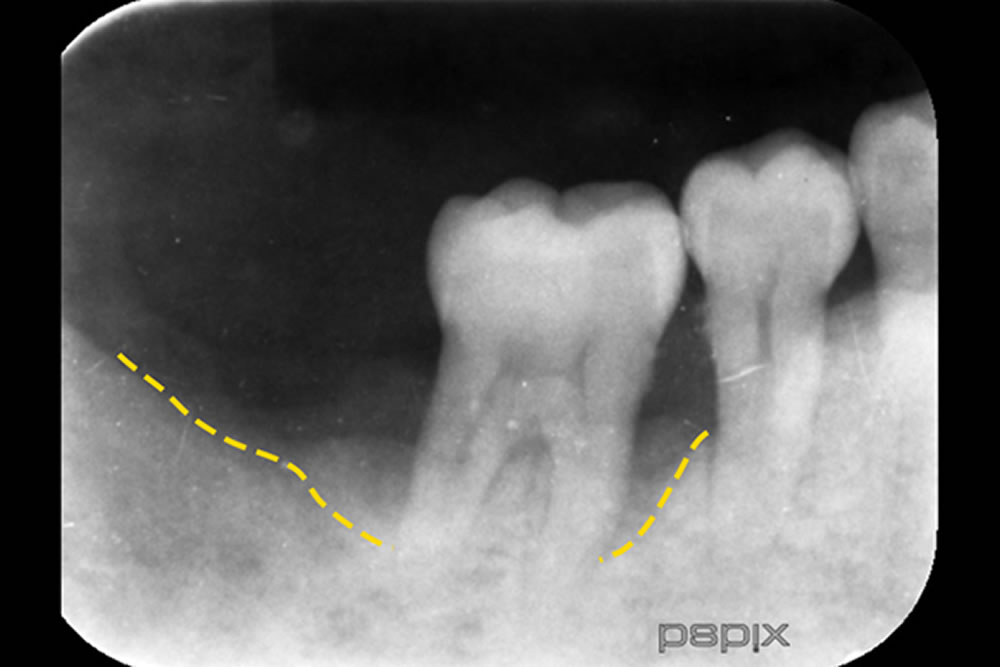

レントゲン検査の結果、歯の周囲の骨が大きく失われている状態が確認されました。そこで、できるだけ体への負担を抑えるために「MINST(低侵襲非外科治療)」という方法を選択しました。これは歯ぐきを一切切らずに行う治療で、再生材料なども使用せず、自然治癒力を活かした方法です。